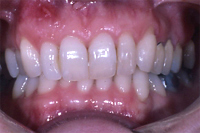

Die Abb. 1 bis 4 sollen als anschauliche Beispiele für gesunde und kranke Fundamente dienen.

Ein 31 Jahre alter Patient zeigt einen starke Zahnfleisch-Rückgang im Oberkiefer (Abb. 1 und 3) und wir beschliessen, diese Rezessionen zu behandeln.

Der Erfolg der Behandlung ist deutlich in den Abb. 2 und 4 zu sehen. Sehr augenfällig konnte die Situation um den Eckzahn im linken Oberkiefer verbessert werden (vergleiche dazu Abb. 3 vorher und Abb. 4 nachher).